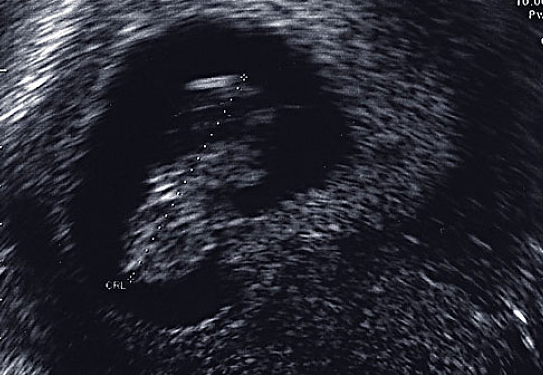

在一個月經(jīng)周期中,月經(jīng)結(jié)束后,卵泡開始發(fā)育,卵泡分泌雌激素,雌激素刺激子宮內(nèi)膜的基底層,子宮內(nèi)膜就會慢慢的生長。到了月經(jīng)中期卵泡成熟,排卵。

排卵后雌激素水平有個短暫的下降。這個時候子宮內(nèi)膜大約有8mm,這個時期的子宮內(nèi)膜叫做增生期的子宮內(nèi)膜。

雖然子宮內(nèi)膜也在長厚,但孕激素抑制子宮內(nèi)膜腺體的無序增生。到月經(jīng)前,子宮內(nèi)膜厚度約達到12-15mm左右。大約排卵后2周,如果沒有受孕,卵巢上的黃體萎縮,不再分泌雌激素和孕激素。雌激素孕激素水平驟然下降,子宮內(nèi)膜中血管斷裂、子宮內(nèi)膜脫落,月經(jīng)來潮。